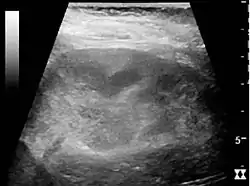

Acute pyelonephritis with increased cortical echogenicity and blurred delineation of the upper pole.[16]

If a kidney stone is suspected (e.g. on the basis of characteristic colicky pain or the presence of a disproportionate amount of blood in the urine), a kidneys, ureters, and bladder x-ray (KUB film) may assist in identifying radioopaque stones.[9] Where available, a noncontrast helical CT scan with 5 millimeter sections is the diagnostic modality of choice in the radiographic evaluation of suspected nephrolithiasis.[17][18][19] All stones are detectable on CT scans except very rare stones composed of certain drug residues in the urine.[20] In patients with recurrent ascending urinary tract infections, it may be necessary to exclude an anatomical abnormality, such as vesicoureteral reflux or polycystic kidney disease. Investigations used in this setting include kidney ultrasonography or voiding cystourethrography.[9] CT scan or kidney ultrasonography is useful in the diagnosis of xanthogranulomatous pyelonephritis; serial imaging may be useful for differentiating this condition from kidney cancer.[10]

Ultrasound findings that indicate pyelonephritis are enlargement of the kidney, edema in the renal sinus or parenchyma, bleeding, loss of corticomedullary differentiation, abscess formation, or an areas of poor blood flow on doppler ultrasound.[21] However, ultrasound findings are seen in only 20% to 24% of people with pyelonephritis.[21]